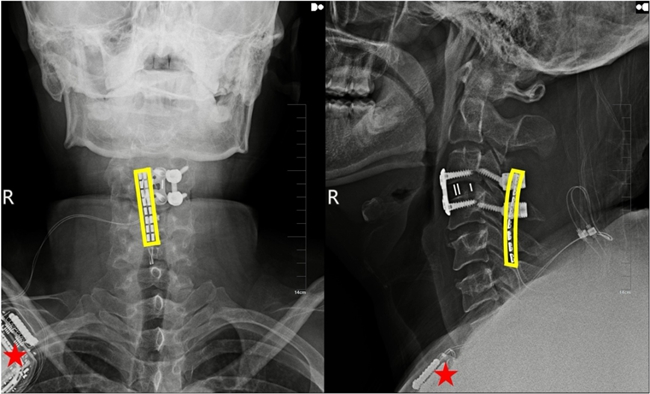

植入術(shù)后X線顯示,黃色方框?yàn)殡姌O位置,星號(hào)為皮下脈沖發(fā)射器位置。